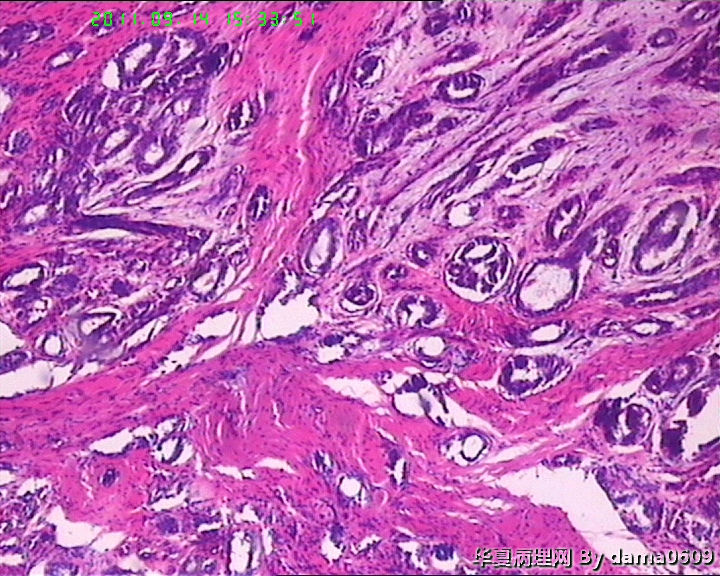

女,22岁,乳腺肿物,病史不详。

不整形软组织肿物一个,V:2.0x1.5x1.5cm。无包膜。切面实性,灰白色,小结节状,质中。

镜下结构复杂,图3、4、8、10、11、12、13、15、17、18、19、20为肿物中央区域,占标本大部分,图1、2、7、14为肿物边缘部分,图5、6、9、16、21为二者交界处。有点乱,不好意思,请老师别介意。

请教老师,诊断:硬化性腺病,可以吗??谢谢!!